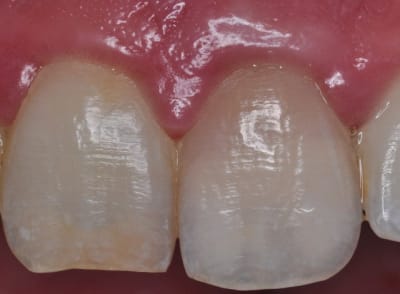

Et voilà mes débuts.

D'abord un cas.... sympa. Première étape, bridge 3 dents antérieur, le patient a un partiel résine qui lui prend les 3/4 du palais pour une bête dent....

Pour la première, la profondeur de champs est pas "top", mais c'est moi qui ai merdé.

Le point AF est sur les centrales.

J'ai rectifié le tir sur les suivants en sélectionnant un point AF latéal, et en faisant le cas échéant une MAP manuelle sur le côté.

Sinon j'ai une question : est-ce qu'avec un flash annulaire en vraie macro, vous avez le même reflet du flash que sur mon cliché des centrales ?

A noter que ce qui joue surement, c'est que je n'ai pas séché les dents, ni la gencive.

Peut-être étais-je trop près ? j'avais mis l'objectif en MAP manuelle, sélectionné le rapport 1:1 qui est obtenu à 28,6cm du sujet....

Ou si c'est le flash qui est trop "intense" au niveau de la LED, pas assez "étouffé" ? (bon un flash à 80€ hein......)